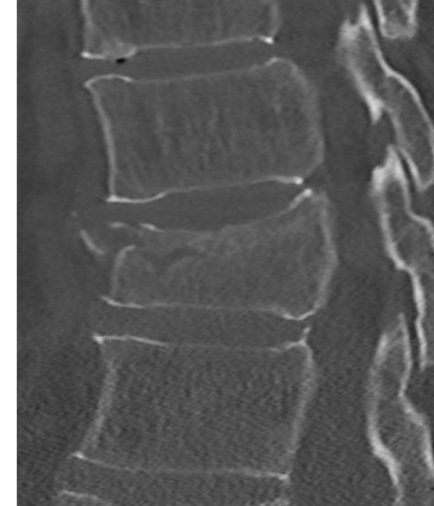

Bij een stabiele wervelbreuk is alleen het wervellichaam gebroken. Als een breuk stabiel is kan het wervellichaam niet verschuiven, waardoor het ruggenmerg niet beschadigd kan raken. Een operatie is dan niet nodig.